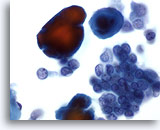

Figure 2

Breast FNA, Benign ductal cells.

Normal breast aspirates yield benign ductal cells, often accompanied by myoepithelial cells. 40x

Figure 2

Breast FNA, Benign ductal cells.

Normal breast aspirates yield benign ductal cells, often accompanied by myoepithelial cells.

40x